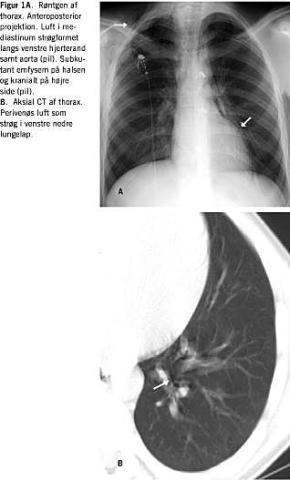

Røntgen af thorax i anterior-posterior-projektion (Figur 1A ) viste luft i mediastinum som vertikale strøg specielt langs venstre hjerterand og aortabuen. På halsen og kranialt på højre side sås subkutant emfysem. Røntgen viste ikke lungeinfiltrater eller tegn på pneumothorax.

Ved en CT af thorax (Figur 1B) sås der luft perivenøst i nedre venstre lungelap. En rumperet perifer bronkie eller alveole kunne således være årsag.

Summary Spontaneous pneumomediastinum: a rare cause of chest pain Ugeskr L&aelig;ger 2004;166:4168-4169 Spontaneous pneumomediastinum is a rare condition caused by a bronchial or alveolar rupture. We present the X-ray and CT findings in a patient in whom the condition occurred after playing soccer. The CT scan demonstrates the position of the alveolar rupture and the passage of air along the veins to the pericardium and mediastinum.